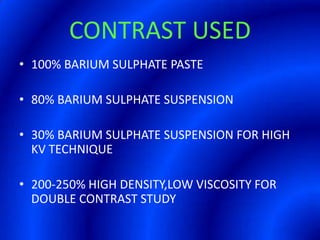

This document provides information about a barium swallow procedure. It begins with an introduction and overview of the embryology and anatomy of the pharynx and esophagus. It then describes the procedure itself, including preparation, technique, views obtained, and indications. Specific conditions that may be examined include pharyngeal and esophageal webs, foreign body impaction, scleroderma, dysphagia, mediastinal masses, and carcinoma. Diagrams are provided to illustrate normal anatomy and various pathological findings.